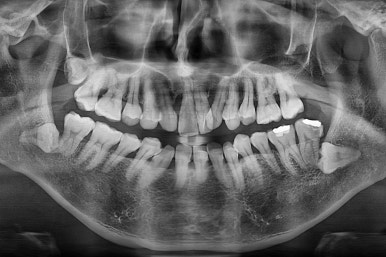

3. 초진 시 X-ray 분석

기본적인 파노라마 사진으로 치아 갯수, 뿌리 상태 등을 파악하고 CT 영상을 통해 골결손 부위, 비강 및 기도의 형태까지 파악해 줍니다.

특히 결손 부위 파악이 중요한 이유는 다음과 같습니다.

치아 이동 계획에서 결손 부위로는 치아를 움직이지 말아야 하며

해당 부위로의 이동이 생기면 잇몸/뼈의 결손 및 관리가 안될 수 있습니다.

입천장의 결손 부위가 악궁확장 시, 코와 입천장이 뚫려버리는 일도 생길 수 있습니다.

결손 부위의 결손 치아를 추후에 보철로 갯수를 추가할 때, 임플란트는 안되고 뼈의 안정성이 떨어지므로 특별한 주의가 필요합니다.